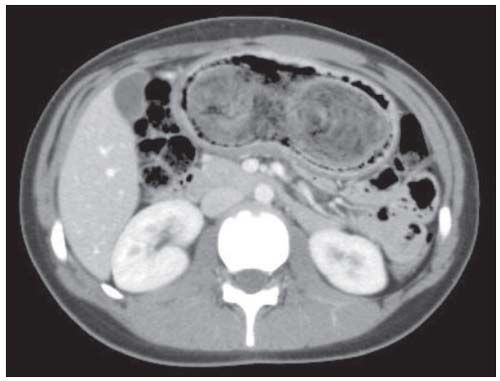

Figure 1 – Axial CT scan shows a large, bilobed, heterogeneous mass within the stomach. The mass has a laminated appearance and is outlined by air bubbles.

Mononucleosis from possible exposure was the presumptive diagnosis; however, results of a rapid heterophile antibody test were negative. Liver function panel, complete blood cell count, erythrocyte sedimentation rate, and serum uric acid levels were all within the normal range. An abdominal ultrasonogram revealed an epigastric mass and normal spleen. Abdominal CT scan findings were indicative of a large gastric bezoar (Figures 1 and 2), which was promptly removed by laparotomy, without complication.